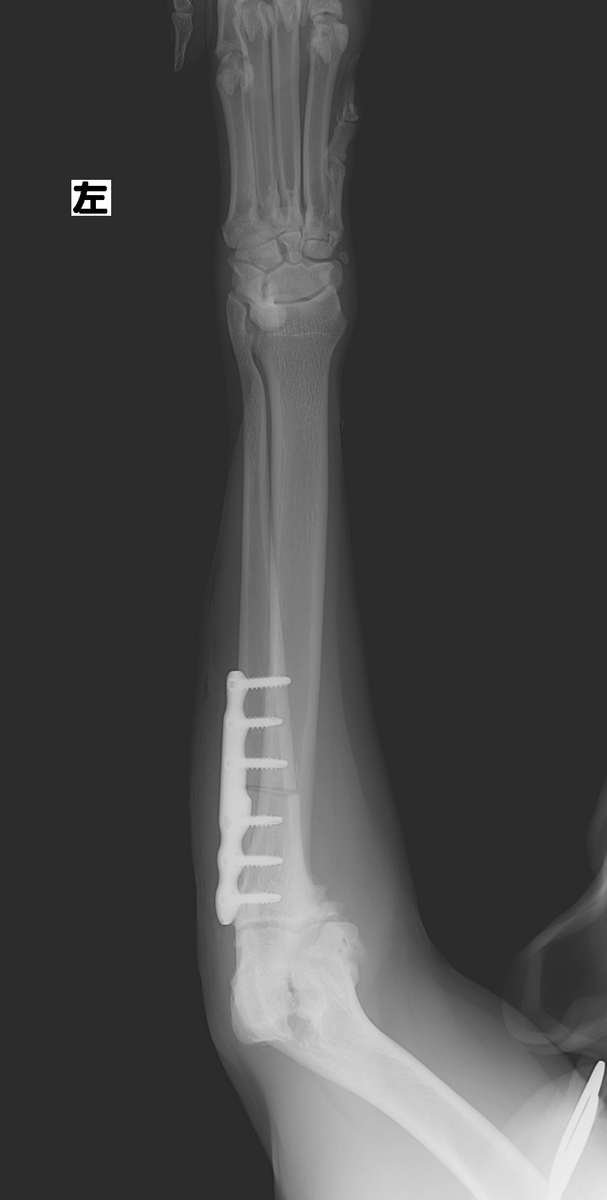

治療は、PAUL (近位尺骨外反骨切り術)という手術を実施しました。

この手術は、前腕の尺骨近部を骨を切って、角度を変える事により体重を内側から外側へ変化させる方法です。これにより、内側にかかる負担を軽減することができます。